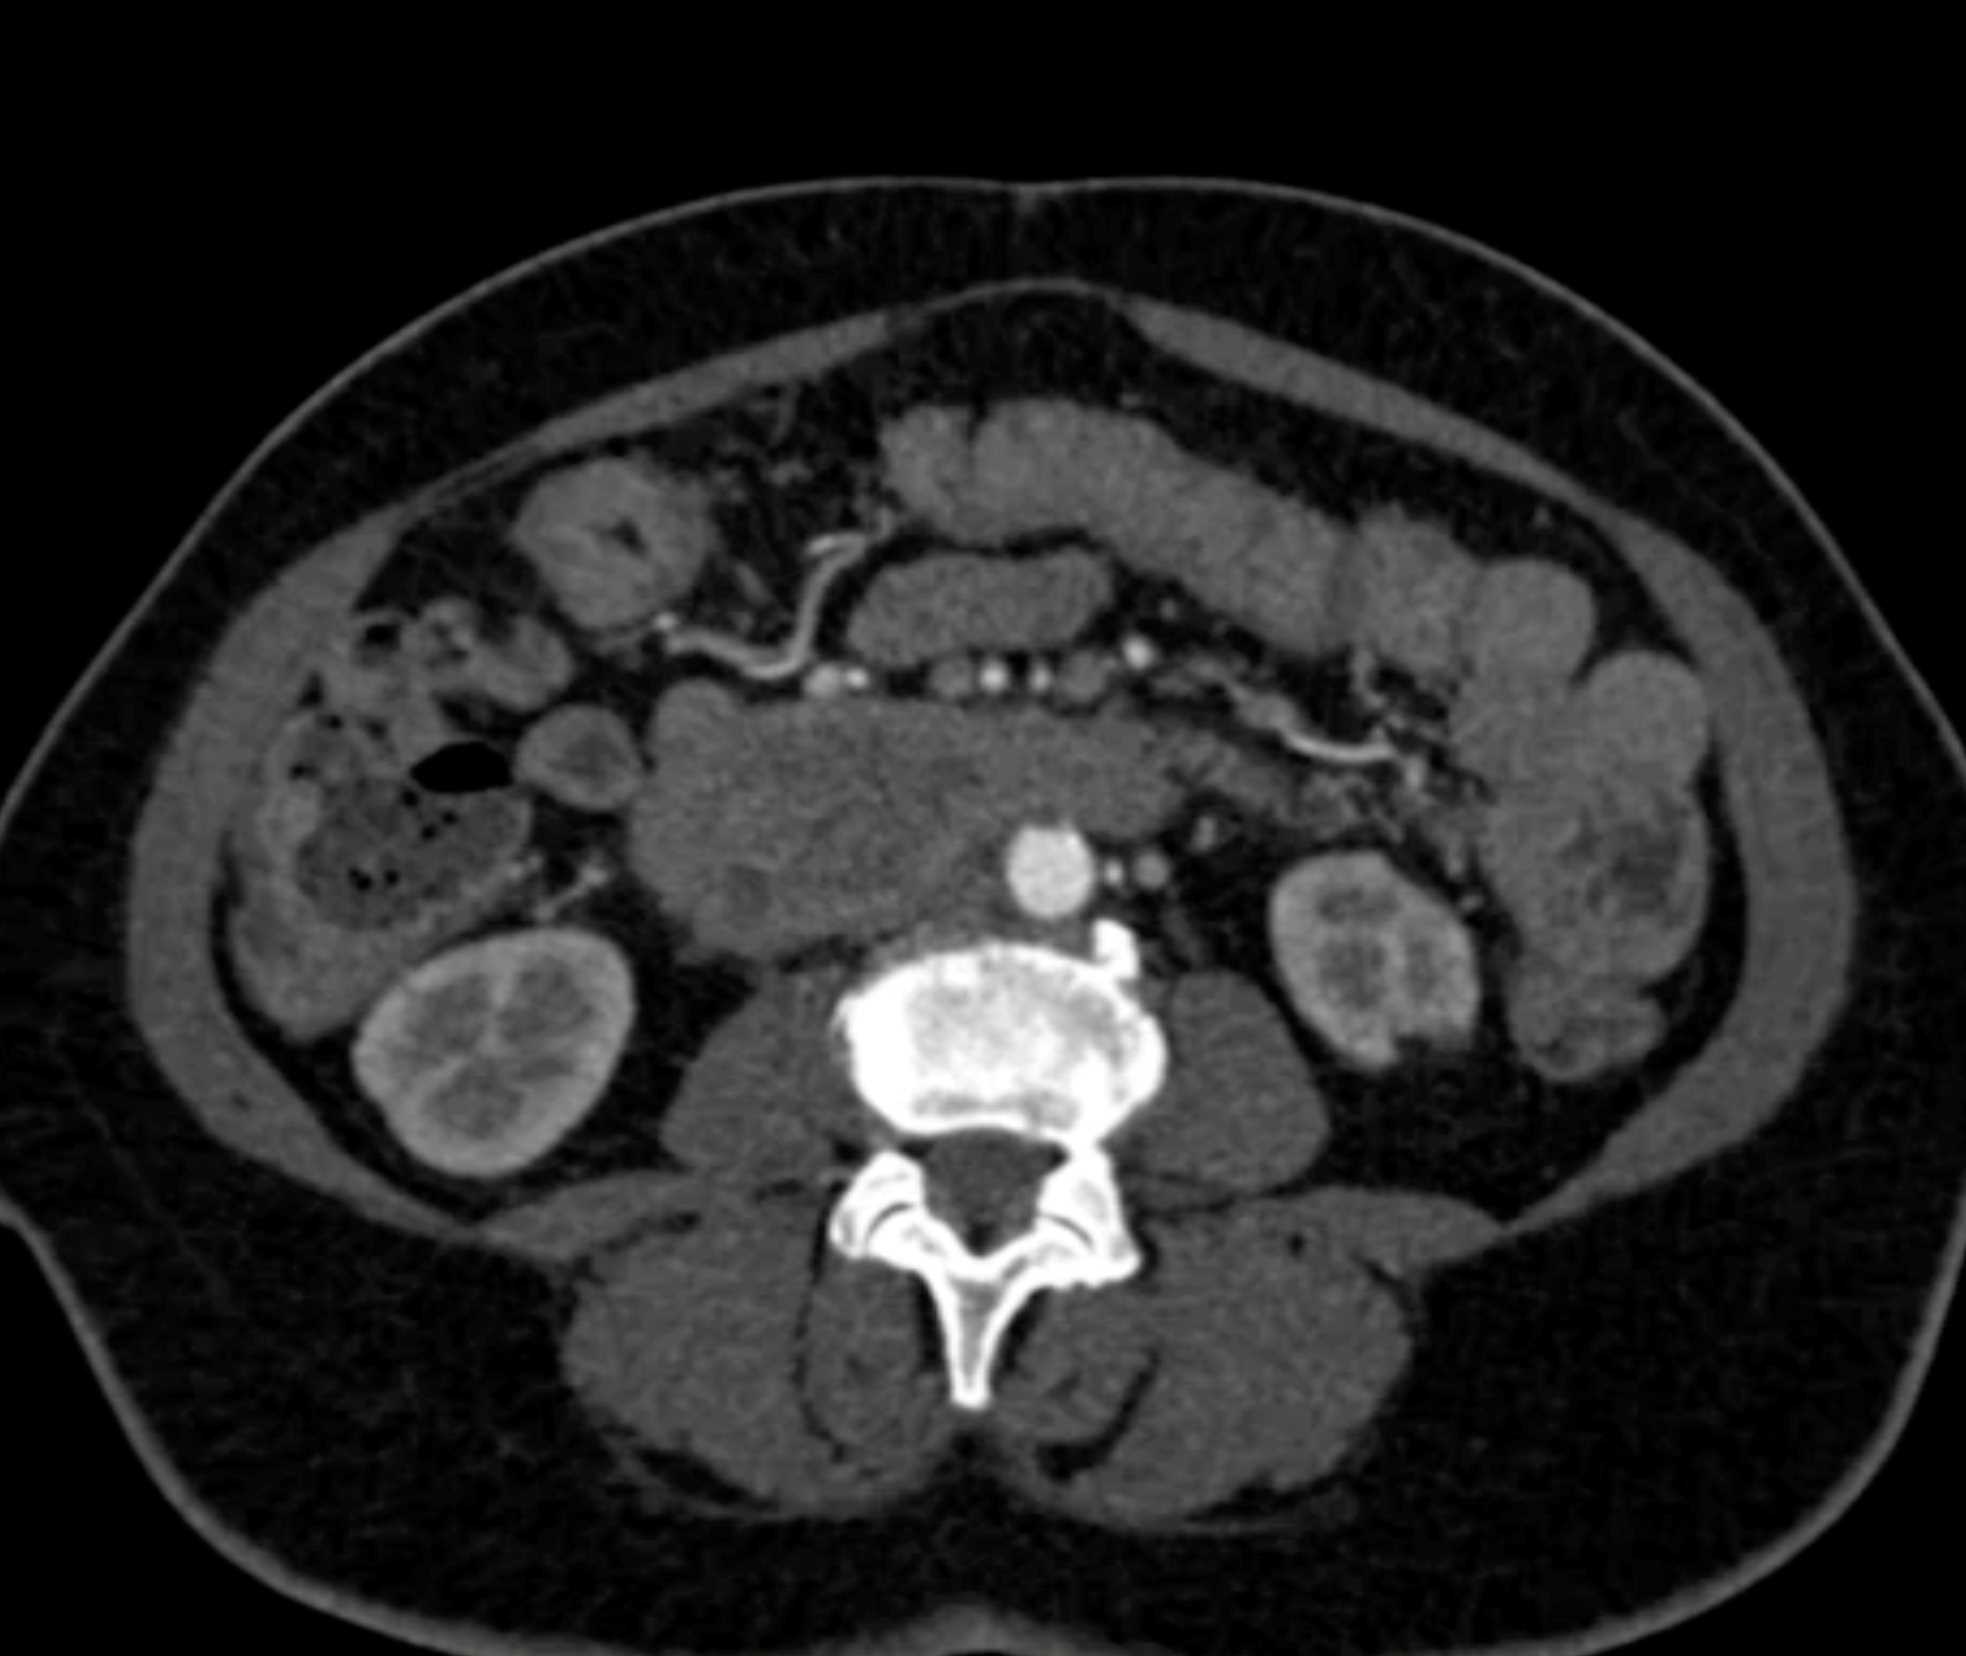

Lagre Gastric GIST Tumor